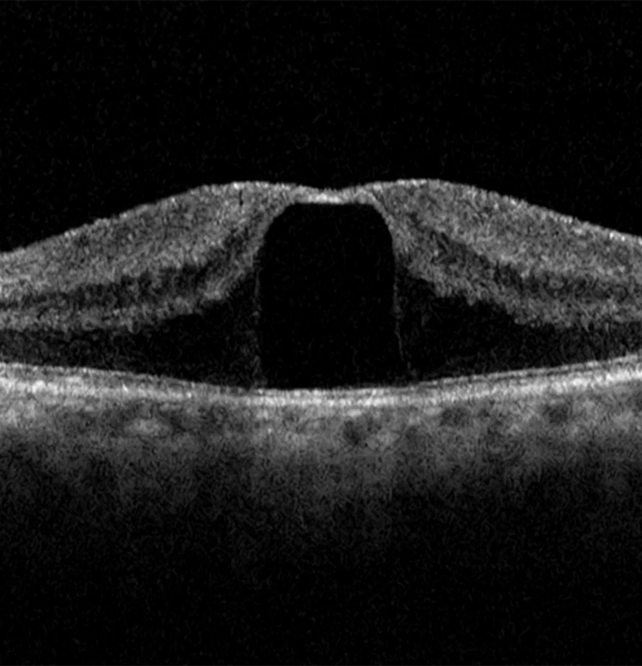

Macula is the central part of the Retina, due to certain factors that is aeging changes, macular oedema or trauma there may develop a defect in thr central part called “Macular Hole”.

Diagnosis :- Retina Evaluation , OCT (Optical coherence tomography).

Treatment :–Surgical treatment with Pars Plana Vitrectomy performed as early as possible.